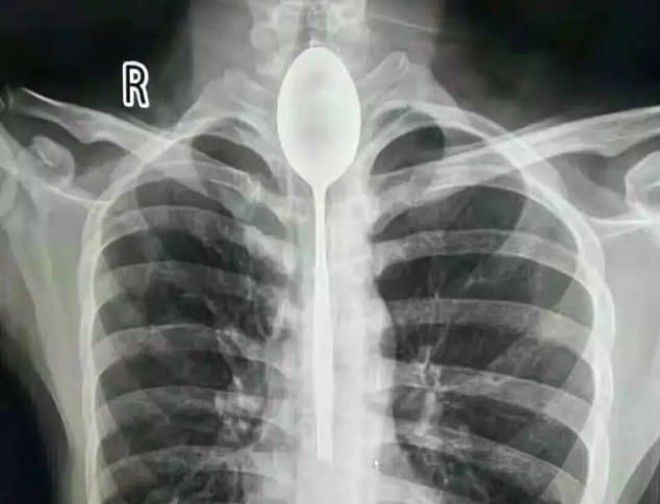

К моменту поступления Чжана его пищевод уже загноился. Операция по извлечению ложки через рот длилась 2 часа и проводилась под общим наркозом.